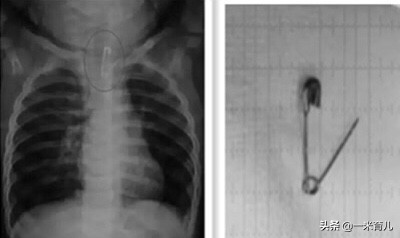

所以,家长对儿童的看护是十分重要的,儿童是否有吞食异物史能为儿童消化道异物的诊断提供最直接、最快速的证据,怀疑异物摄入的儿童一般需要行X片、CT等检查来确定。

儿童吞食曲别针